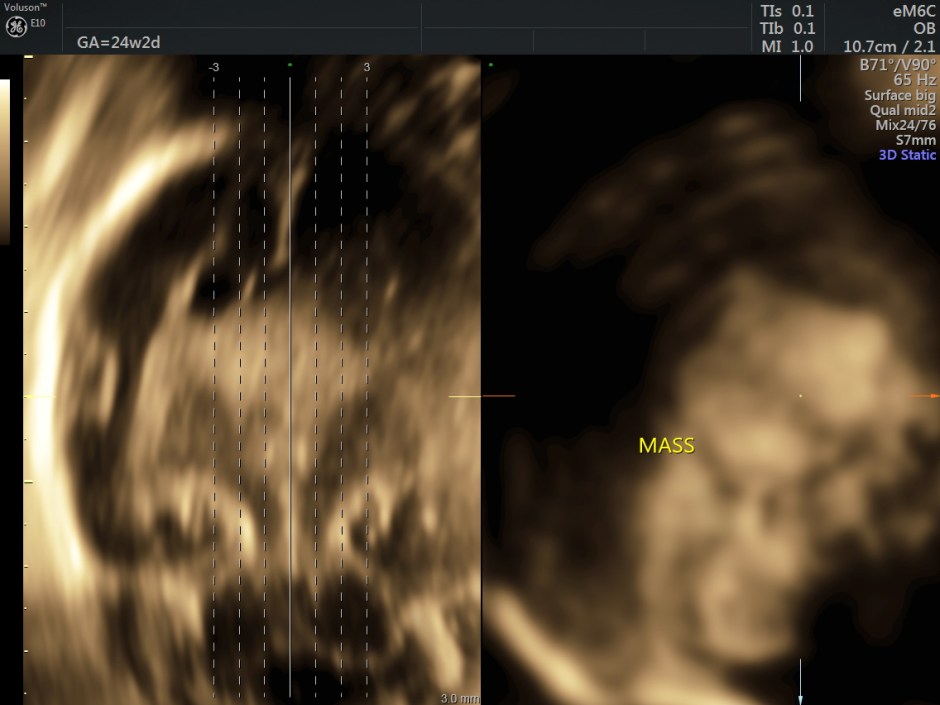

A careful look at the 3rd ventricle shows a solid mass.

Some reconstructed images are given below.

Choroid plexus papilloma (CPP) is a rare and benign tumor composed of epithelial cells that line the ventricular choroid plexus and correspond to 0.4%-0.6% of fetal intracranial tumors. CPP may develop in the lateral ventricle, third ventricle, and fourth ventricle. It is generally diagnosed during the third trimester and is always associated with unilateral or bilateral ventriculomegaly. CPP has slow growth and noninvasive behavior; however, because of its specific location, CPP can block the drainage of cerebrospinal fluid and cause hydrocephalus.

An echogenic mass involving the choroid plexus is visualized on US and MRI. Color Doppler imaging may be useful to show vascularization in the lesion.